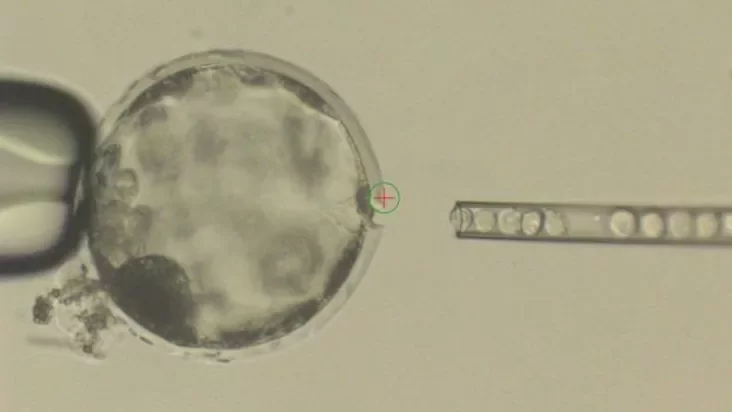

Ученые вживляли человеческие стволовые клетки в эмбрионы свиньи. В результате получалась смесь из человеческих и свиных клеток, которую на месяц подсаживали самке свиньи.

Этот процесс оказался очень неэффективным: из 2 075 подсаженных эмбрионов в течение 28 дней развивались лишь 186 штук. Однако при этом были признаки того, что человеческие клетки продолжают функционировать как часть химеры.

«Впервые человеческие клетки росли внутри крупного животного», — объяснил один из авторов исследования профессор Хуан Карлос Исписуа Бельмонте из Института биологических исследований Солка.